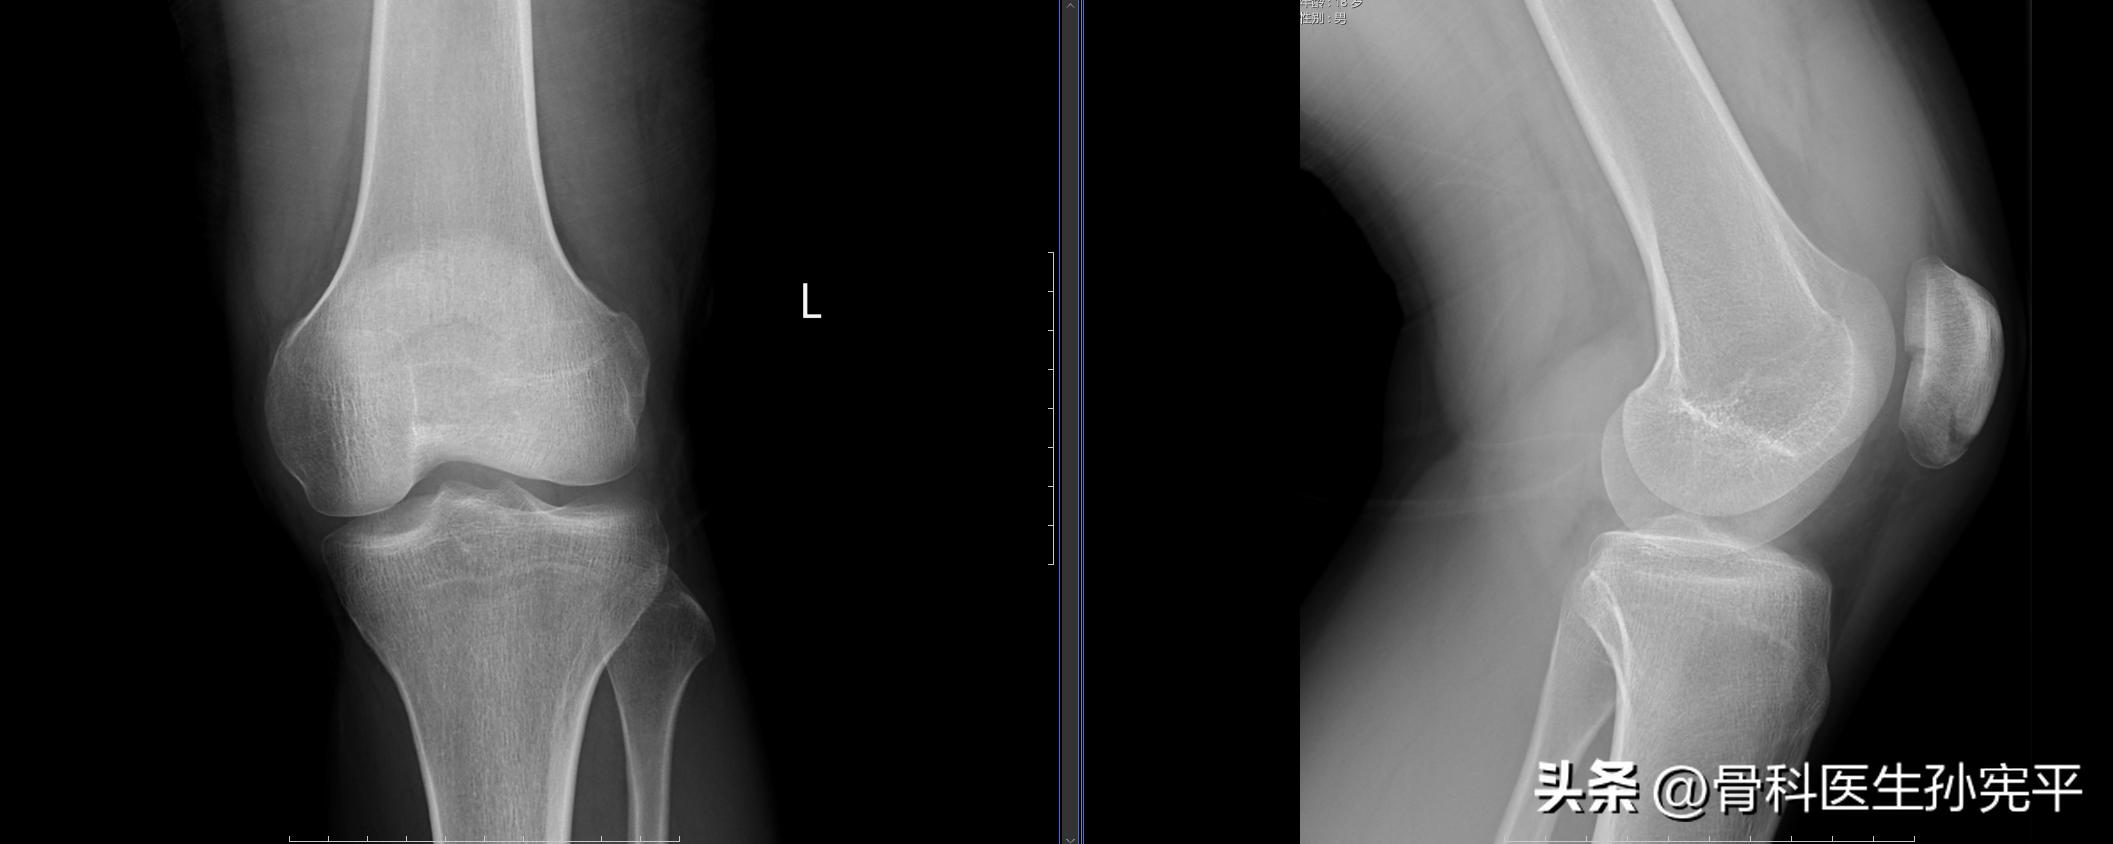

病例3:外伤后左膝关节肿痛2小时。

左侧髌骨骨折

阅片可见左侧髌骨骨质结构断裂,髌骨关节面台阶样改变,对于涉及髌骨关节的骨折,关节面台阶大于2mm为手术治疗指征。